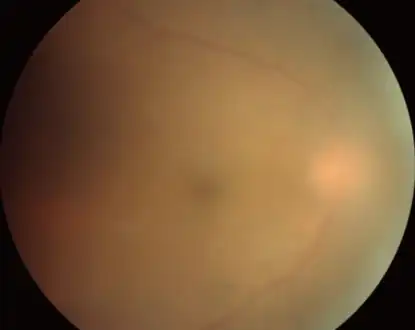

Fundus image of choroidal neovascularization in ocular toxoplasmosis

Infection of the vitreous body in toxoplasmosis of the eye